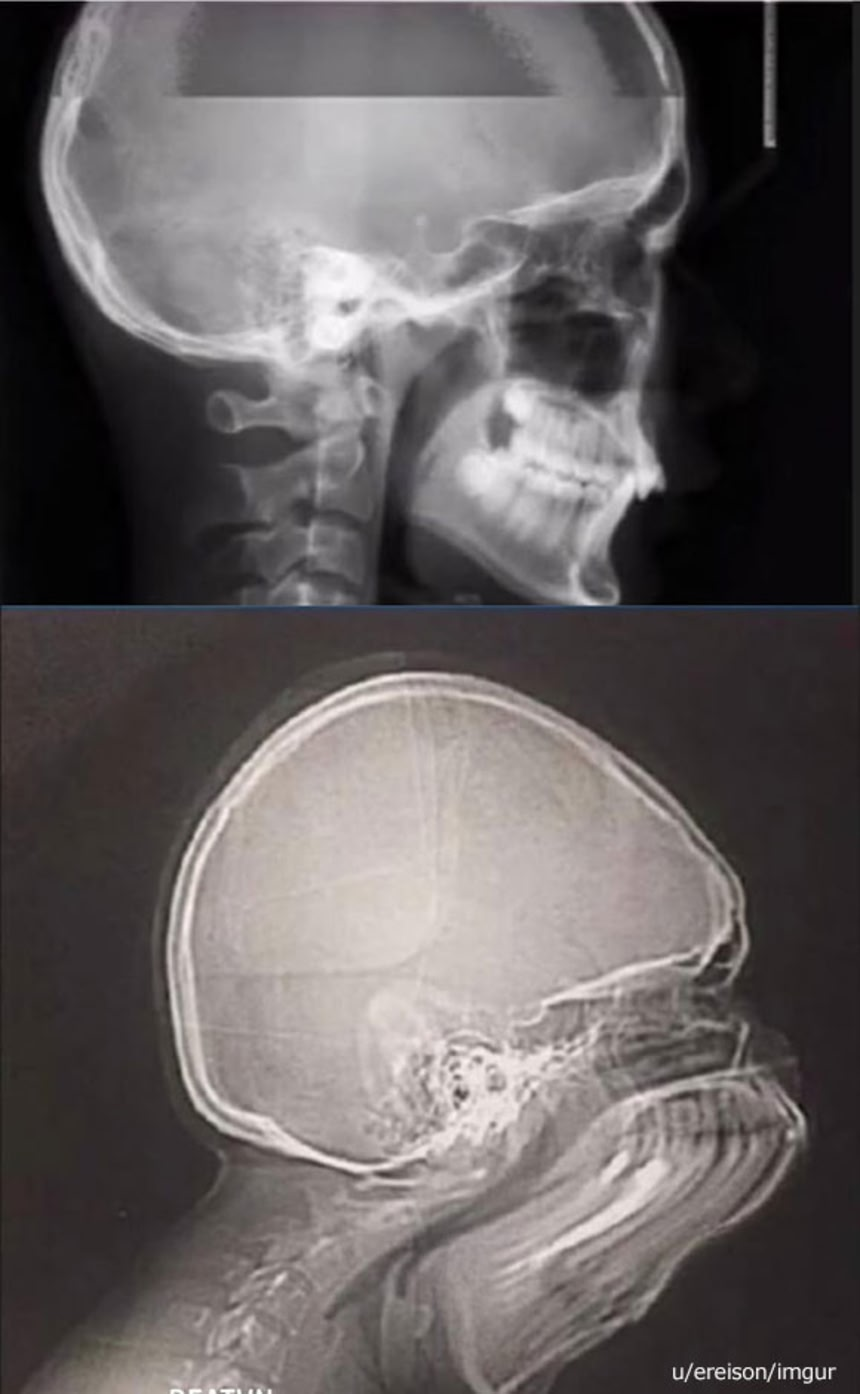

これからお見せする画像は頭部レントゲン撮影中にうっかりクシャミをしてしまったときのものだそうだ。もはや人というよりは、エイリアン…

上の画像は通常に撮影されたもの。

下の画像は撮影中にくしゃみしちゃったときのもの。

・上のはレントゲンだけど、下のは頭蓋骨CTポトグラムかな。レントゲンなら1秒未満で撮影されるけど、CTポトグラム約2~3秒かかる。

これレントゲンじゃなくてCTの位置決め画像じゃねーか

撮影時間が全然違うよ